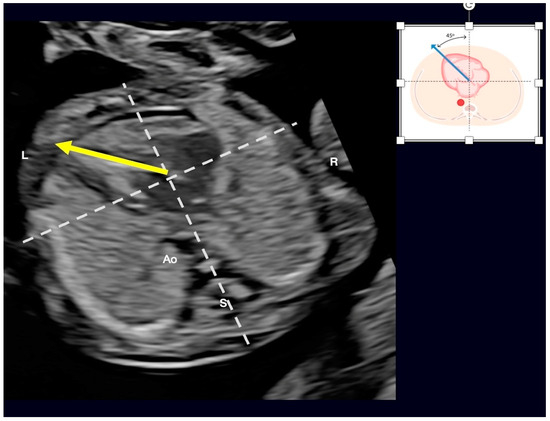

3. Fetal Intelligent Navigation Echocardiography (FINE) and Artificial Intelligence

- Yeo, L.; Romero, R. Fetal Intelligent Navigation Echocardiography (FINE): A Novel Method for Rapid, Simple, and Automatic Examination of the Fetal Heart. Ultrasound Obstet. Gynecol. 2013, 42, 268–284. [Google Scholar] [CrossRef]

- Carrillo, M.C.; Rolo, L.C.; Tonni, G.; Araujo Júnior, E. Evaluation of the quality of standard fetal heart views using the FAST, STAR and FINE four-dimensional ultrasound techniques in congenital heart disease screening. Echocardiography 2020, 37, 114–123. [Google Scholar] [CrossRef]

- Yeo, L.; Romero, R. Color and power Doppler combined with Fetal Intelligent Navigation Echocardiography (FINE) to evaluate the fetal heart. Ultrasound Obstet. Gynecol. 2017, 50, 476–491. [Google Scholar] [CrossRef]

- Yeo, L.; Romero, R. Intelligent navigation to improve obstetrical sonography. Ultrasound Obstet. Gynecol. 2016, 47, 403–409. [Google Scholar] [CrossRef] [PubMed]